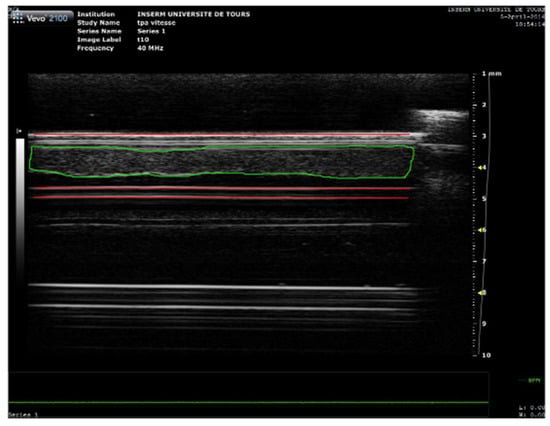

2.5. High Frequency Ultrasound Imaging and SoS Measurement

3.1. Sound Speed Measurement during Sonothrombolysis